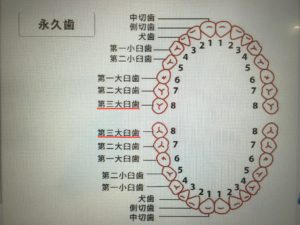

親知らず(第3大臼歯)は、おおむね10代後半から20代前半に生え始めます。

歯列(ヨシダDental Cultureより)